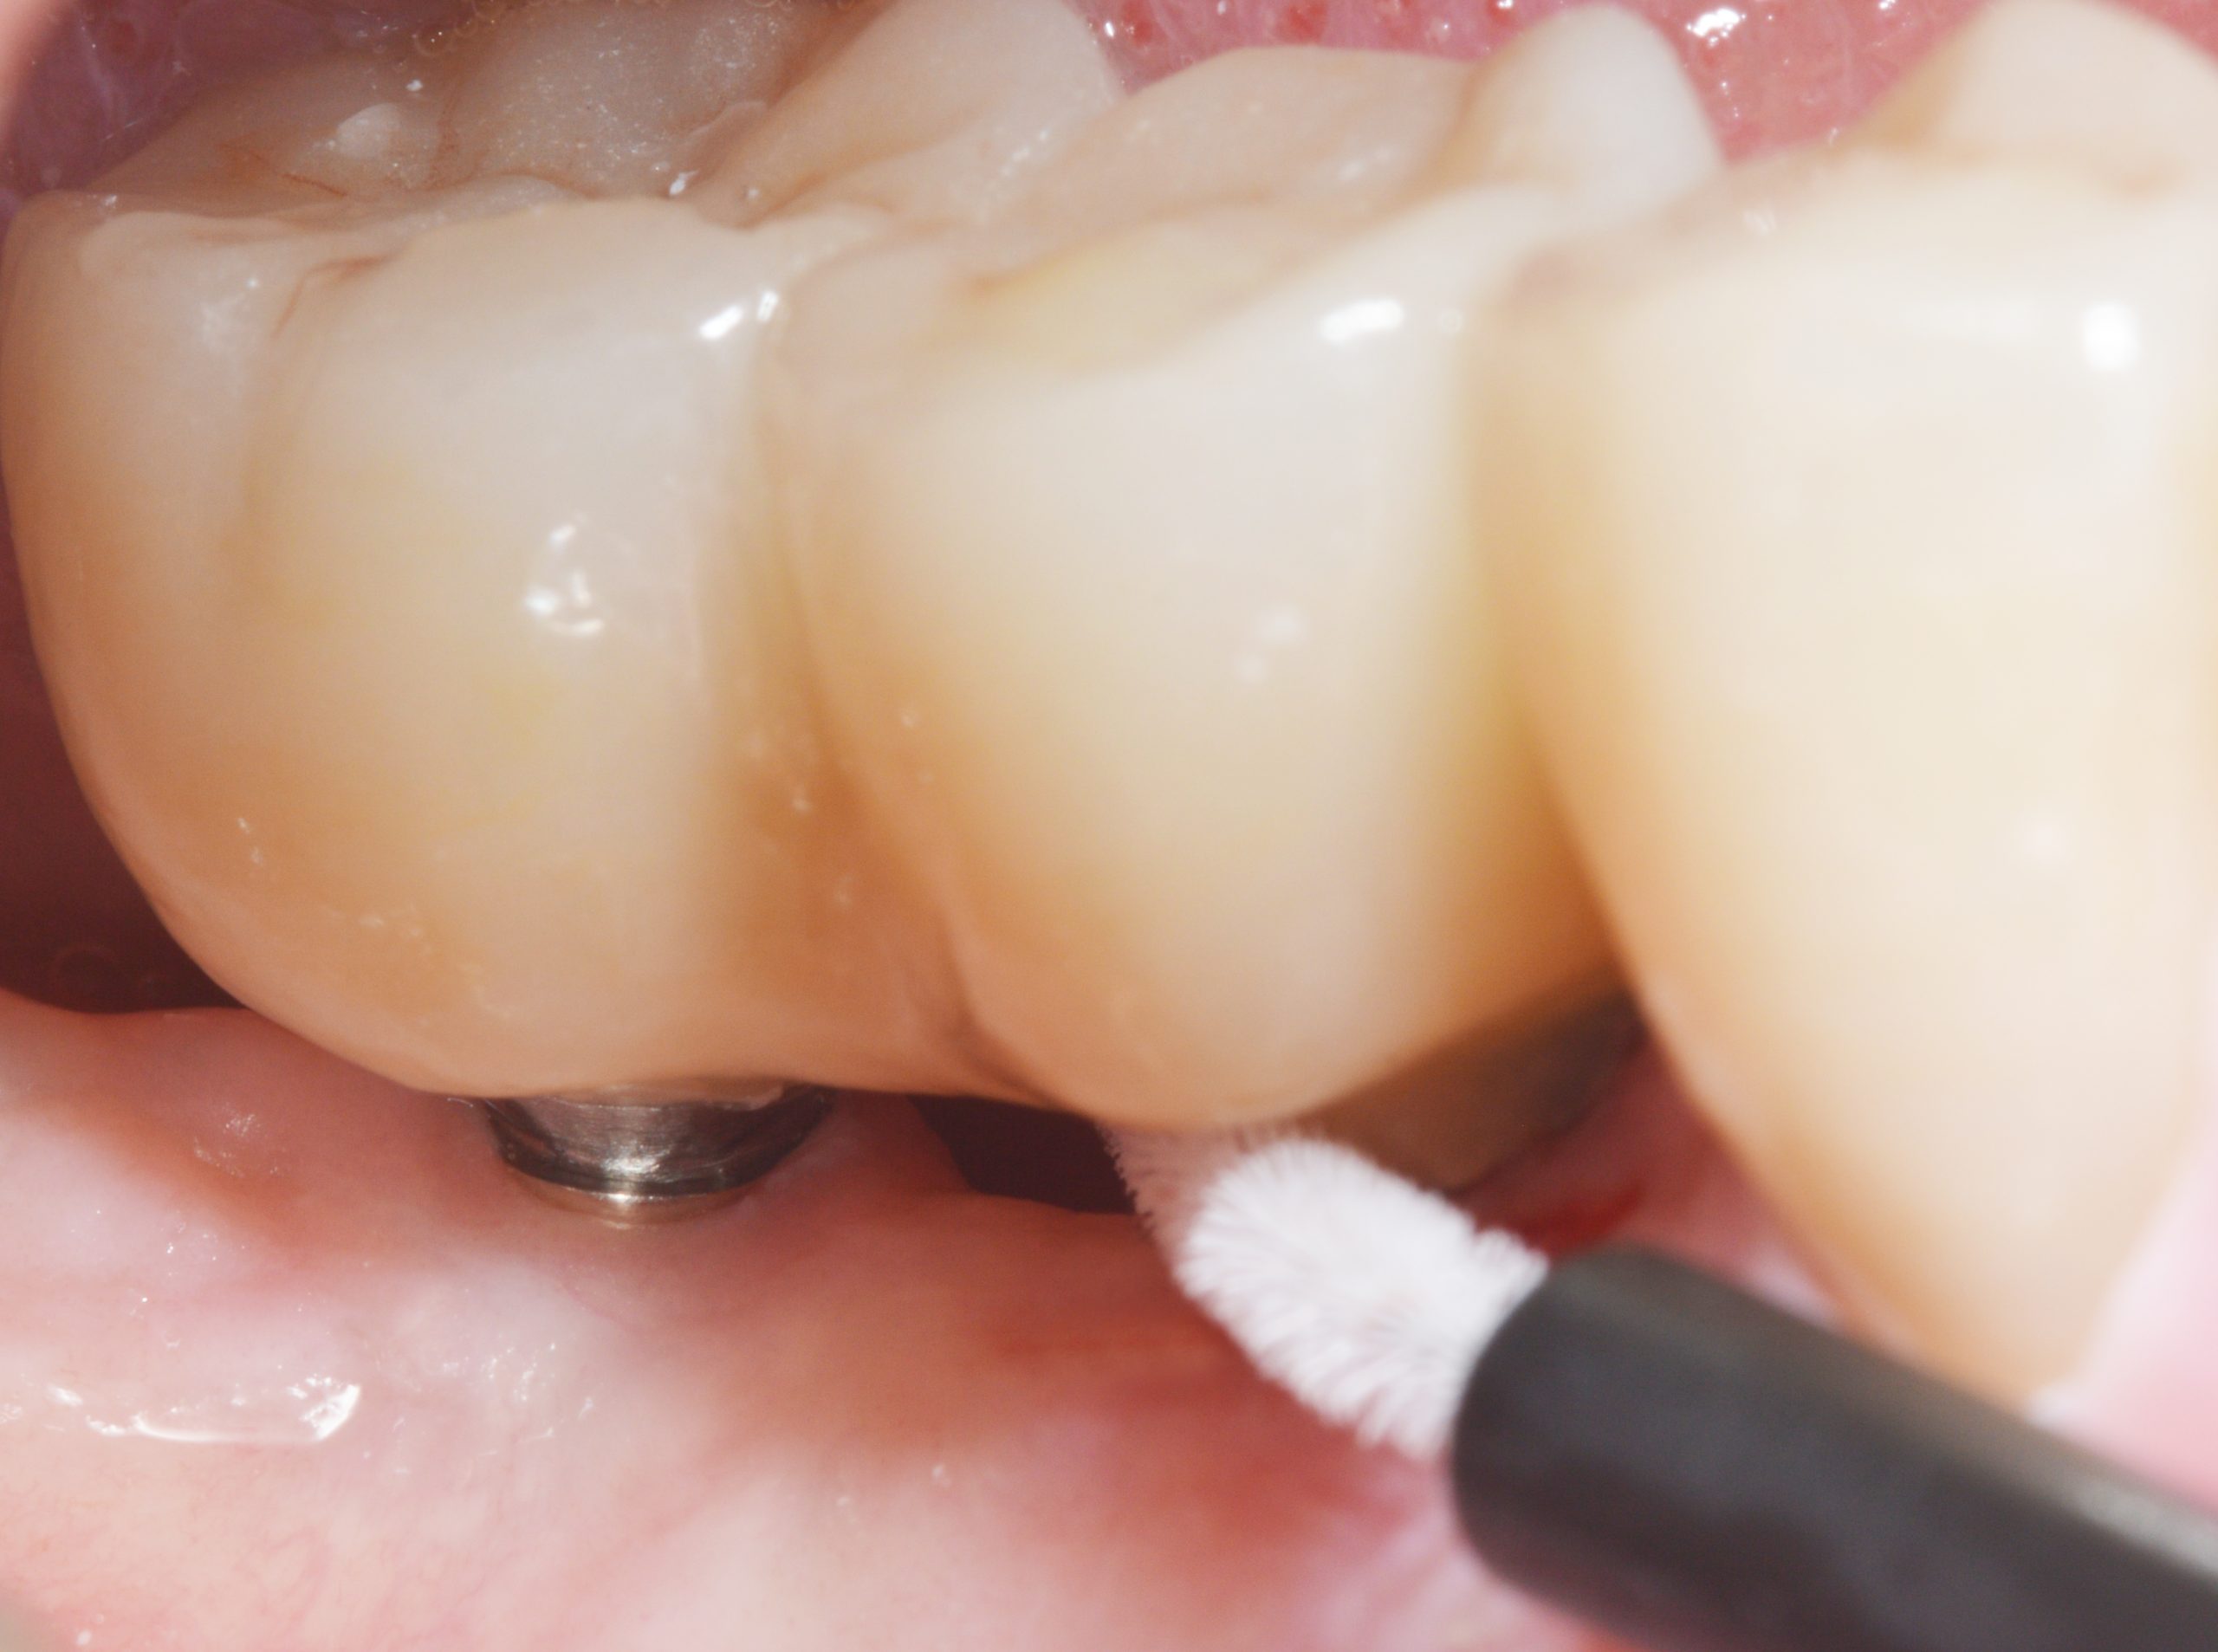

Während der offenen Einheilung wurden Reinigungskontrollen mit der Anweisung, durch Einsatz von Spezialbürsten auch die Abdeckschrauben zu säubern, um eine entzündungsfreie periimplantäre Gingiva sicherzustellen, durchgeführt.

Zusätzlich sorgte die Zahntechnik für einen reinigungsfreundlichen Durchgang basal zwischen 45 und 46. Die Handhabung der Interdentalbürsten wurde kontrolliert und der Patient mit entsprechenden Instruktionen in das regelmäßige Recall entlassen.